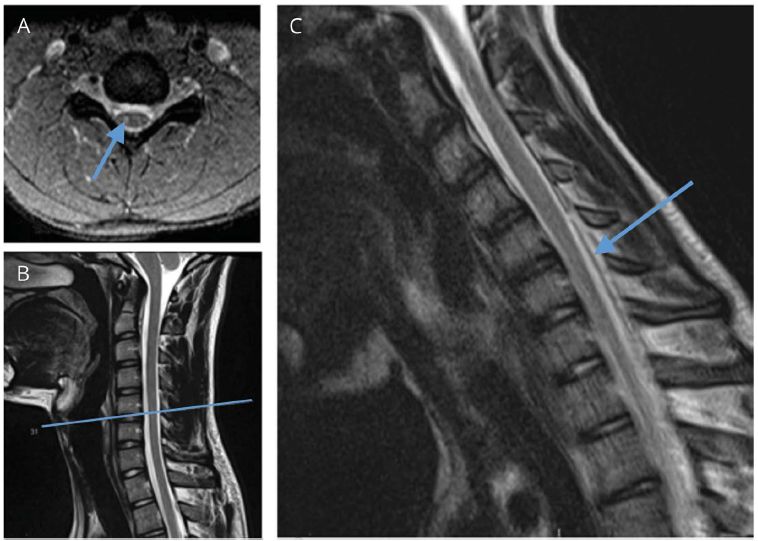

颈髓萎缩的发现提示神经元丢失。鉴于对HD的怀疑,患者还进行了屈颈位颈椎MRI检查,结果显示颈髓C5-7水平轻度变薄;屈颈时硬脊膜前移,脊髓变扁(图2)。 因此,临床过程、影像以及电生理检查均支持HD的诊断。

图2 影像检查结果

A和B:T2加权相显示颈髓萎缩区域(B)存在点状高信号(短箭头)(A);

C:T2加权相屈颈位可见硬膜囊前移(长箭头)和脊髓变扁。